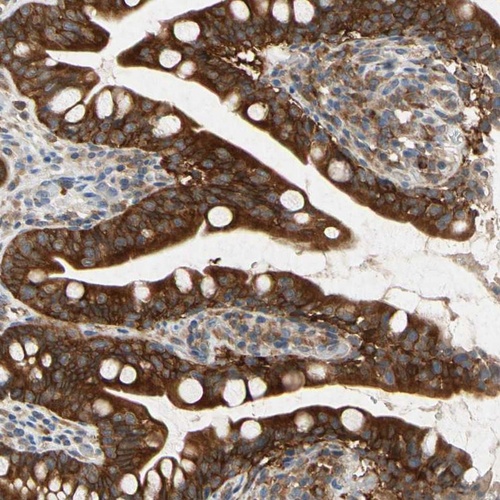

Immunohistochemistry analysis in human small intestine and skeletal muscle tissues using Anti-RPS6KA1 antibody. Corresponding RPS6KA1 RNA-seq data are presented for the same tissues.